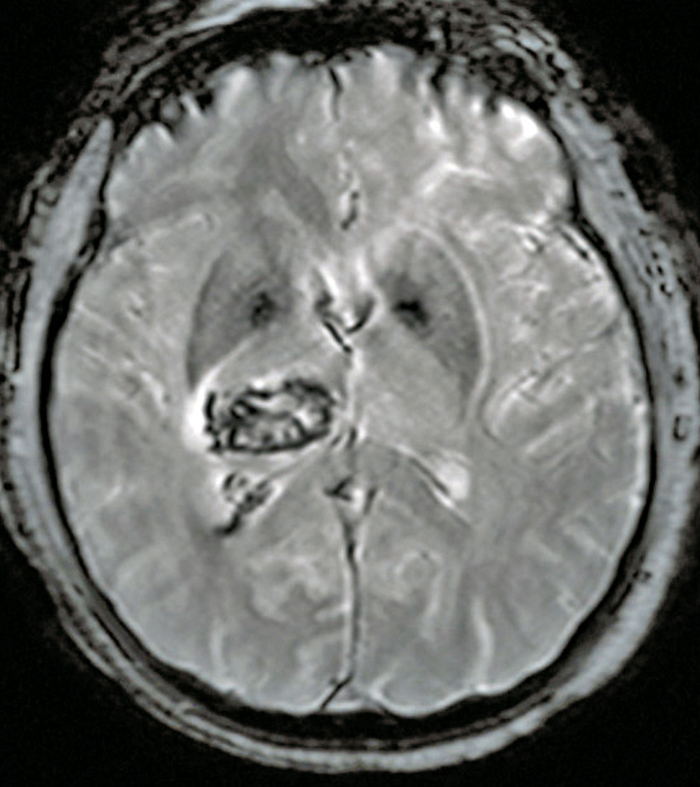

Quel est votre diagnostic ?

Il s'agit d'un hématome intracérébral thalamique droit en IRM séquence T2*. L'hématome intracérébral est une collection de sang consécutive à la rupture d'un vaisseau intracrânien. L'hypertension artérielle est la première cause et l'hémorragie est alors très souvent localisée au niveau des noyaux gris centraux. La deuxième cause est la rupture d'une malformation vasculaire, que ce soit une malformation artérioveineuse, un anévrisme ou un cavernome. Parmi les autres causes, on cite la thrombophlébite cérébrale, les troubles de la coagulation et l'angiopathie amyloïde. Le scanner cérébral, qui est l'examen de référence en cas d'hémorragie cérébrale, met en évidence une plage en hyperdensité et est le plus souvent complété d'un scanner cérébral avec injection et d'un angioscanner cérébral à visée étiologique (recherche de tumeur, de malformation vasculaire, de thrombose veineuse cérébrale). L'IRM cérébrale avec ARM peut être intéressante lorsque le scanner n'est pas contributif pour rechercher une cause de l'hémorragie.